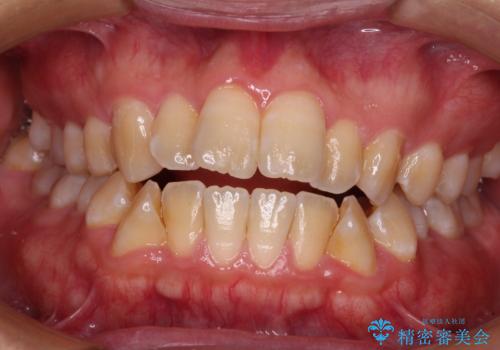

【非抜歯】上下の前歯が噛み合わないオープンバイトの治療

開咬と前方に飛び出した前歯 インビザラインによる矯正治療

担当医 藤巻太一朗